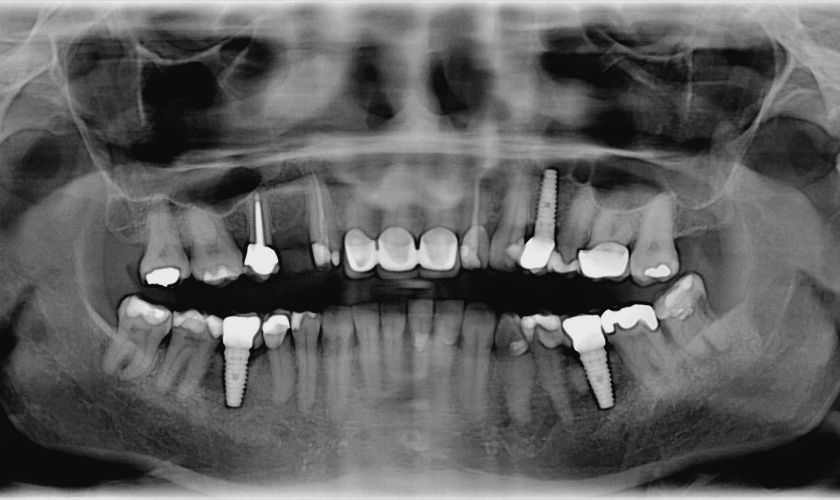

- Realiza radiografías de control si es necesario.

Las limpiezas realizadas por el profesional son diferentes de las higienes convencionales. Se utilizan instrumentos específicos (de titanio, plástico o teflón) que eliminan la placa sin dañar la superficie del implante.